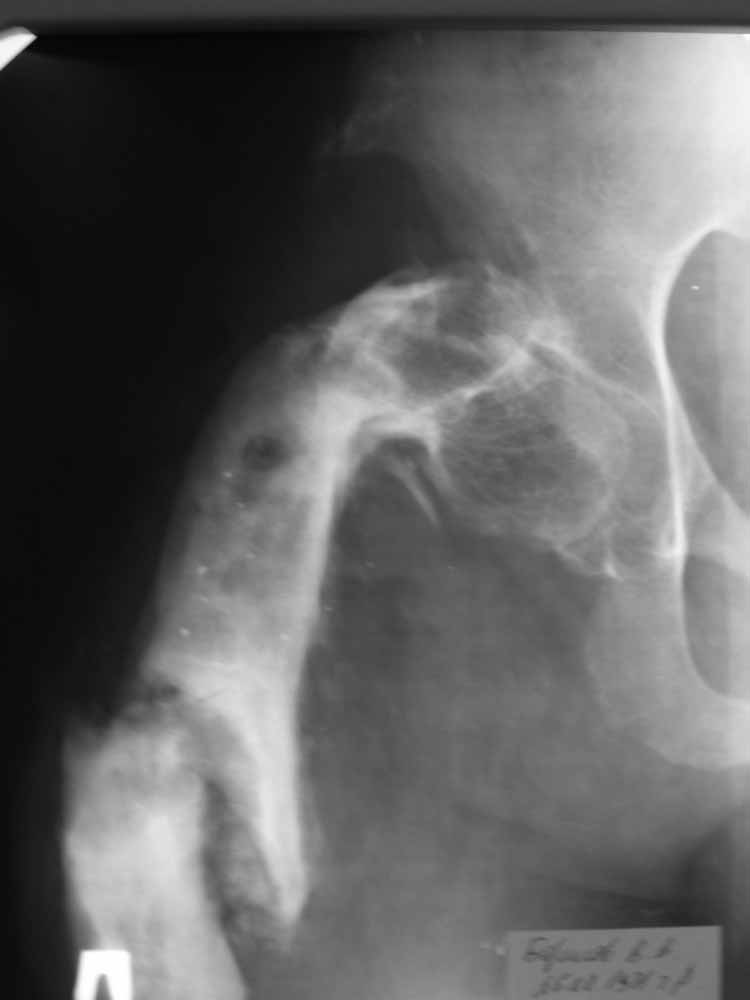

Пациент 29 лет. Неоднократно оперированная Coxa Vara.

В анамнезе этапные операции по поводу устранения Coxa Vara, формирование артродеза коленного сустава, удлинения бедра. В данный момент беспокоит укорочение 7 см, эквинус стопы. Объективно: - местный статус виден на фото, сосудистых и неврологических расстройств нет. Обратился в консультативном порядке, настроен на удлинение голени в г.Волгограде. (со слов больного - не берут без санации очага на голени). Ваши предложения? Из кулуарных соображений - а не актиномикоз ли это? Иссечение рубцов+ VAC+ Стержень с аппаратом + микрососудистый трансплантат(?)

Ваш вопрос, коллега, вполне правомерен. В советское время те из нас, кто занимался костно-гнойной инфекцией видели достаточное количество подобных несчастных, кочующих из стационара в стационар. Своеобразный госпитализм приводил к тому, что люди тратили всю свою, как правило достаточно короткую жизнь, на лечение зачастую реально неизлечимых процессов. В данном случае имеющаяся рентгенологическая картина груботрабекулярной перестройки кости, сочетающаяся с участками склероза говорит, скорее всего, о том, что вся имеющаяся картина, дополненная чудесными фотографиями,вполне укладывается в клинику гематогенного остеомиелита, которым и страдает пациент с детства. Никакие санации, к сожалению, не приведут в данном случае к излечению, так как все имеющиеся рубцы являются зоной жизни этой самой инфекции. При продолжении лечения не исключено достаточно раннее развитие амилоидоза в этом случае. Мне кажется, что оптимальным было бы определить пациента в институт протезирования и протезостроения или в то учреждение, которое в регионе выполняет данную функцию. Специалисты помогли бы определиться с уровнем ампутации, являющейся, по сути, единственным способом разорвть порочный круг и дать пациенту возможность какой-то социальной адаптации. А в плановом порядке, насколько мне известно, можно добиться неплохого финансового обеспечения под протез конечности по квоте. Другого решения здесь нет. С уважением, Андрей Волна

извините за очепятку - не берут без санации очага на бедре. Сейчас имеется отделяемое из нижнего свища с периодическим выходом секвестром в виде мелкой крошки. Движений в ТБС почти нет - есть только сгибание градусов до 10. В стопе - только качательные.